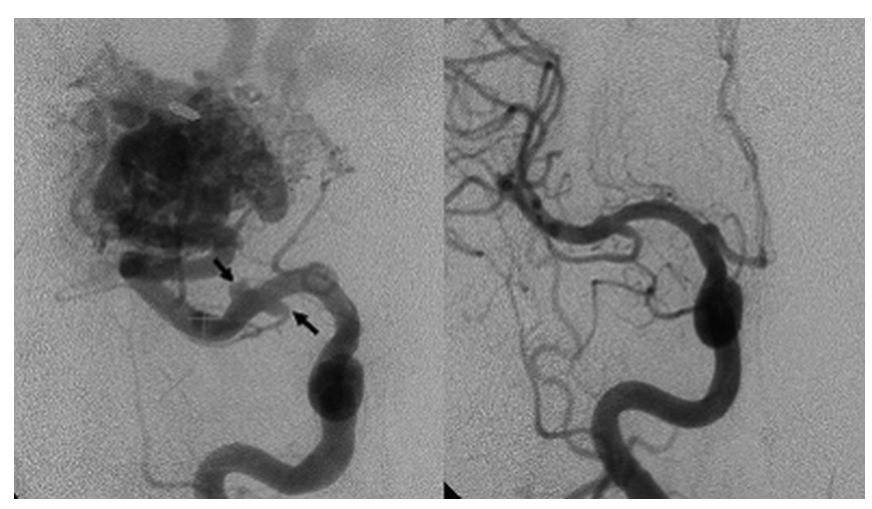

病例三:左图提示该患者的右侧大脑中动脉的 M2 节段存在右侧颞下 BAVM 和 2 处远端 FAs(箭头)。右图显示GKS 治疗37 个月后远端 FAs 完全闭塞,流经 BAVM 和 FAs 供血血管的血流正常化。